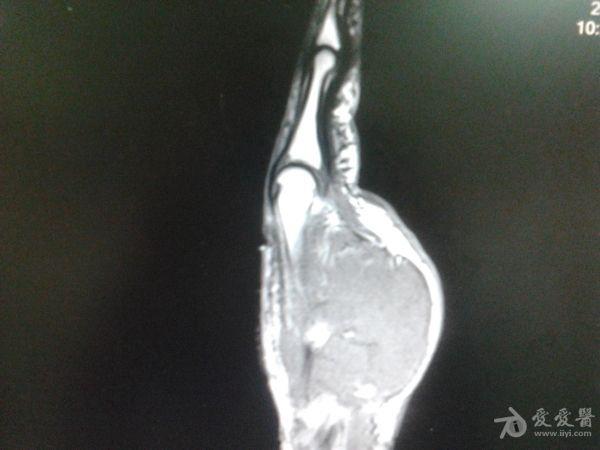

右第一掌骨、大多角骨肿瘤

男性患者,81岁,右手肿痛3个多月。无任何其它症状。体查:右手第一掌骨部肿胀明显,第一指活动受限,余四指活动可,腕关节活动小部分受限,活动时会痛。影像学检查如下。活检示:弥漫性大B细胞淋巴瘤。大家看看需不需要截肢?现在有人主张手术;有人主张不手术,直接化疗。大家有什么看法?

从以上资料看已经影响到腕关节了,还是截吧,不能姑息